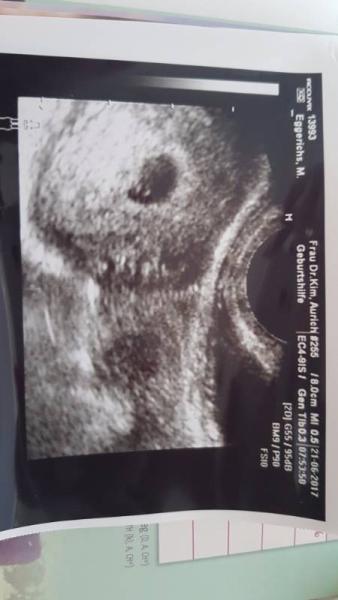

War ja gestern wegen unterleibsziehen im KH. Alles sieht soweit gut aus, nur meinte die Ärztin sie kann noch nicht viel erkennen, sie erhane nur einen Dottersack. So jetzt habe ich mir mein Ultraschall Bild fotografiert und ganz nah rangezoomt. Und da konnte ich was sehen. Vielleicht spielen meine Augen mir einen Streich..... was ich sehe ist ein hellgrauer Schatten, sieht aus wie ne Bohne. Hoffe ihr könnt was erkennen, müsst euch den Schwarzen Kreis anschauen und konzentriert!?

Hier nochmal Orginal

Huhu. Das kann gut sein, dass das die embryonale Anlage ist. Als Laie halt schwer zu sagen. Wie weit bist du denn? LG

Ich seh nur eine leere fruchthöhle.

Am Tag des Ultraschall war ich 5+6 ssw. Heute bin ich in der 6+1 ssw. Hätte ja sein können das ihr auch was erahnen kontet Naja diese Ungeduld und Ungewissheit mach mich ganz Kirre. Noch 2 Tage Gedulden dann weiß ich mehr. Danke trotzdem fürs schauen

So sah es bei mir aus bei 5+0 kannst ja mal vergleichen